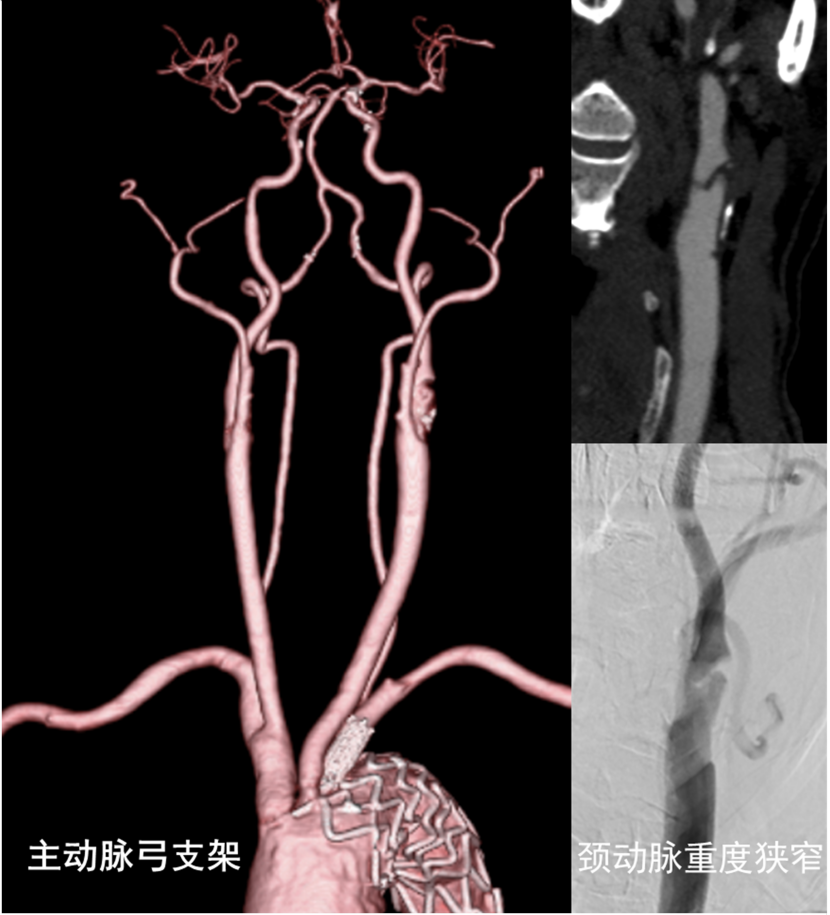

68岁的闵老伯(化名)反复头晕,右侧肢体麻木无力两月余,检查发现左侧颈内动脉重度狭窄。闵老伯曾经进行过主动脉弓支架治疗,无法再接受常规介入治疗。上海交通大学医学院附属仁济医院南院区神经外科团队联合超声医学科、麻醉科、手术室等多学科,让血流“临时改道”,用颈动脉血运重建术解决复杂缺血性脑血管救治难题。

颈动脉狭窄是缺血性脑卒中的常见病因之一,当颈动脉狭窄大于70%时,脑梗死的风险显著升高。对症状性颈动脉狭窄,置入颈动脉支架是常用治疗方法。然而,该手术需要通过股动脉或桡动脉进行支架置入,必须经过主动脉弓。闵老伯曾因主动脉弓夹层进行过支架治疗,主动脉弓里的支架阻碍了常规颈动脉手术路径,治疗陷入僵局。

为此,神经外科团队联合麻醉科、手术室、超声医学科、放射科等专家全面评估了各种手术方式的风险与可行性,最终决定采用最新的颈动脉血运重建术。该技术绕过主动脉弓,直接在颈动脉实施手术。

神经外科主任医师张晓华介绍,颈动脉血运重建术直接绕过主动脉弓,利用特殊装置将血流“临时改道”,使手术时脱落的斑块碎片被直接“吸走”,不流向大脑,防止术中斑块脱落导致脑栓塞的风险,尤其适用于主动脉弓病变或有手术史的患者。